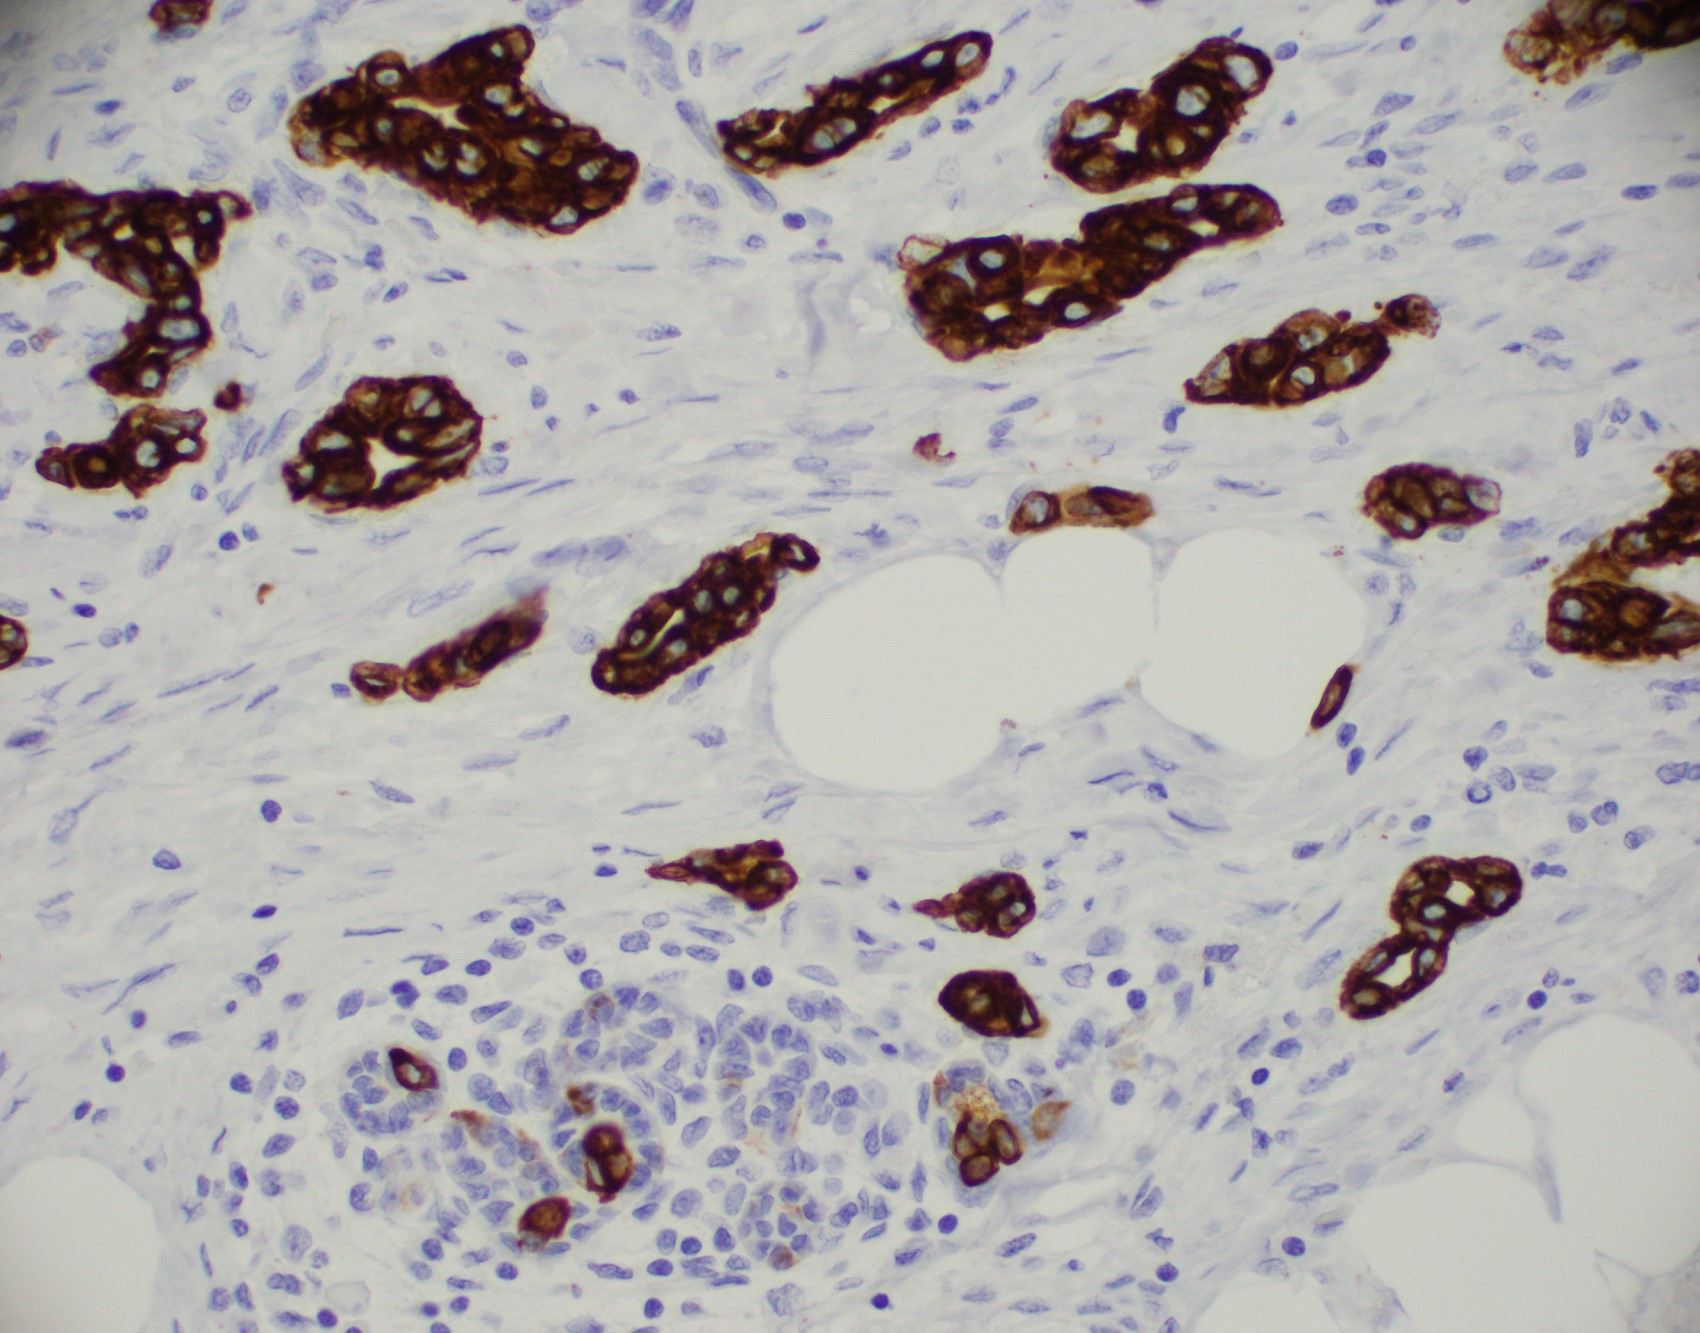

Microscopic (histologic) images

Contributed by Julie M. Jorns, M.D., Kristen E. Muller, D.O., Gary Tozbikian, M.D. and Emad Rakha, M.D.

- No myoepithelial cell lining (as seen in DCIS or benign lesions)

- Endothelial lining is present and is CD31+, ERG, D2-40+, CD34+ and factor VIII+

- Luminal low molecular weight cytokeratins (CK8 / 18, CK19 and CK7 and pancytokeratins such as AE1 / AE3, CAM 5.2, MNF-116), EMA, E-cadherin, p120, ER (60 - 80%), PR (50 - 70%), HER2 (15 - 20%) (Am J Clin Pathol 2006;125:377)

- Myoepithelial markers: p63 (positive in benign lesions), CD10, calponin (Am J Surg Pathol 2001;25:1054, Mod Pathol 2002;15:397)

- IHC using myoepithelial markers shows retained myoepithelial cell layer

A. Calponin and p63. The use of myoepithelial markers is most useful for distinguishing in situ from invasive carcinoma. Utilization of 2 myoepithelial markers, including both a cytoplasmic marker (e.g., calponin or smooth muscle myosin) and a nuclear marker (p63 or p40) is recommended, as myoepithelial expression can be patchy or attenuated (p63 / p40) and show nonspecific expression in endothelial cells (SMMS); the combination of 2 markers provides increased sensitivity and specificity. Both DCIS and invasive breast carcinoma (NST) may show expression of hormone receptors, HER2 and cytokeratins.